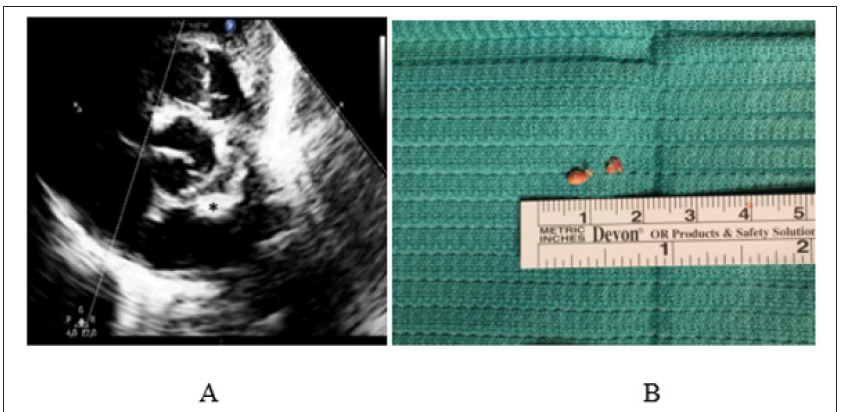

Figure 4: Calcified Amorphous Tumor of The Heart (CAT).

A. Preoperative Two-Dimensional Echocardiogram Showing A Club-Shaped (Asterisk) Left Atrial Mass, With Very Thin Pedicle and Extremely Mobile Appearance.

B. Intra-Operative View of The Gross Anatomic Aspect of The Mass and Pedicle, Subsequently Diagnosed as CAT at Histological Examination.

Surgical mortality occurred in one patient who required postoperative support with veno-arterial extracorporeal membrane oxygenation (V-A ECMO) and iNO, because of refractory hypoxia. Six days after weaning from ECMO, he died because of sepsis and recurrent respiratory failure. Overall mortality (2/6, 22%) was similar between operated and non-operated group of patients with one case observed in each group, since we considered as “nonoperated” the newborn presenting with a diffusely infiltrating and non resectable tumor, who died because of severe biventricular dysfunction and obstruction (Figure 3). Histological examination of the mass was performed in all surgically managed patients. It revealed 2 cases of familial fetal type of rhabdomyoma, 1 rhabdomyoma, 2 myxoma and 1 calcified amorphous tumor (CAT) of the heart (Figure 4), (Table 2).